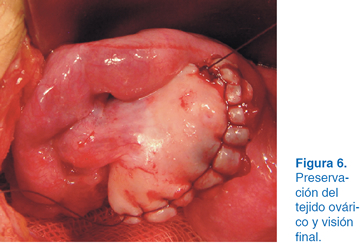

A los dos años del evento quirúrgico en el USG se apreció una tumoración en el ovario izquierdo con dimensiones de 10 x 12 cm (Figura 1). Se solicitó tomografía axial computarizada (TAC), observándose tumoración con densidades mixtas con diagnóstico probable de teratoma (Figura 2). Se optó por laparotomía exploradora donde se identificó el útero y se apreció tumoración dependiente de ovario izquierdo (Figura 3). Se realizó planeación de incisión (Figura 4), posteriormente tumorectomía (Figura 5) y salvamento de tejido ovárico (Figura 6). El reporte transoperatorio mostró teratoma monofásico con bordes libres de tumor.